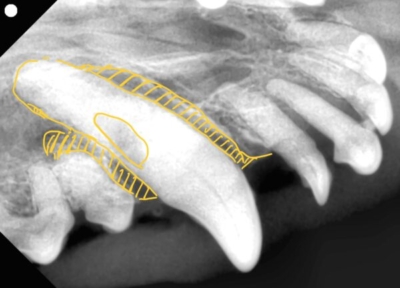

右上の犬歯

黄色斜線部が歯周病で周りの骨が溶けてしまっている状態。口腔鼻腔ろうになっていた。

歯科レントゲンでも犬歯の一部に欠損があるのがわかりますね。これは頭部レントゲンで撮影した部分と一致します。